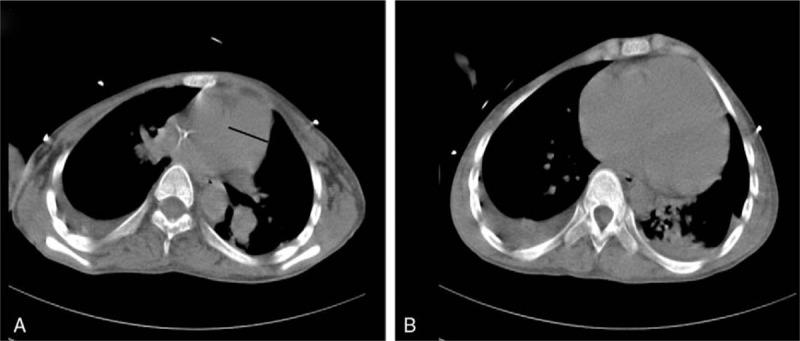

We reported the case of a 15-year-old boy who presented with shortness of breath and exercise limitation after a cold, and the diagnosis of pulmonary hypertension was confirmed by right heart catheter. Other examinations, such as blood tests, high- resolution chest computed tomography scan, and pulmonary function test, excluded other associated diseases as causes of pulmonary hypertension.

我们报告了一名15岁男孩的病例,他感冒后出现呼吸急促和运动受限,经右心导管检查确诊为肺动脉高压。其他检查,如血液检查、高分辨率胸部计算机断层扫描和肺功能测试,排除了其他作为肺动脉高压病因的相关疾病。